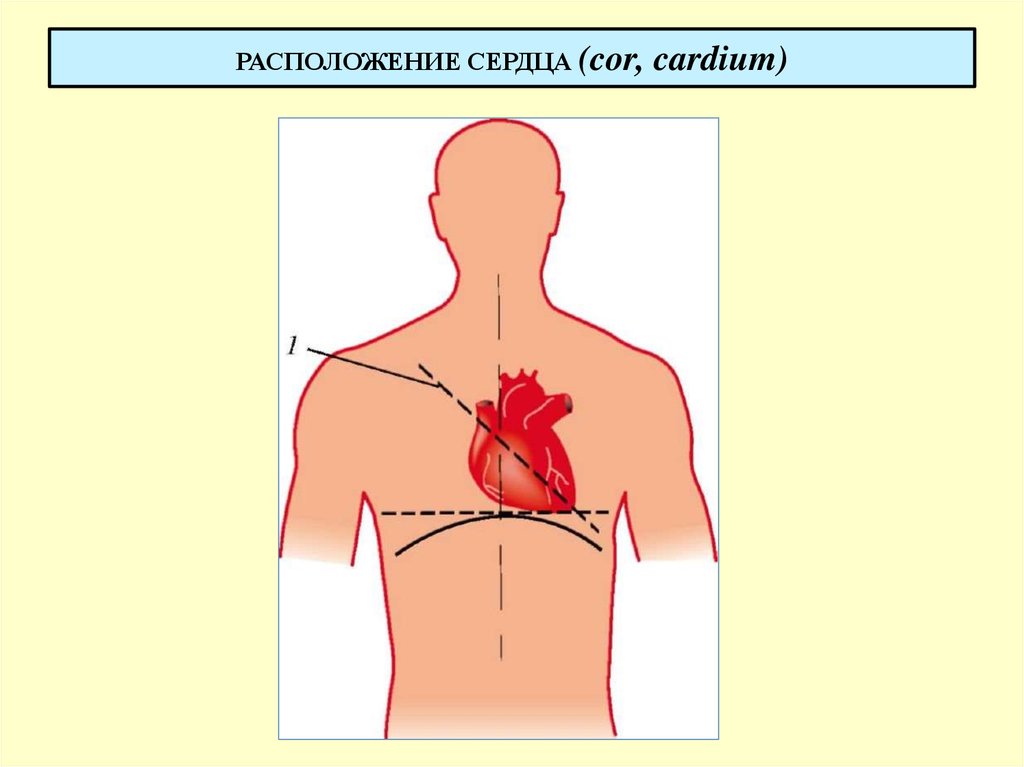

Расположение сердца у человека.

Анатомическое расположение сердца.

Сердце в грудной клетке расположено.

Где расположено сердце у человека анатомия.